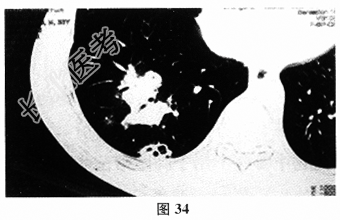

- [材料题] 患者男,46岁,以“肺部感染”收入院。患者2个月前出现咳嗽,痰不多,无发热。胸部CT可见“右下肺散在片状影,并可见空洞形成”(图34)。抗感染治疗(头孢呋辛、左氧氟沙星等)3周症状无好转,复查胸部CT病灶没有明显好转。查体:体温正常,右下肺可闻及湿啰音,实验室检查:血沉28mm/h,血常规、肿瘤标志物、抗核抗体、血培养、甲状腺功能、肺炎衣原体抗体、PCT、CRP未见异常,T-spot阴性,血清隐球菌荚膜多糖抗原乳胶凝集试验阳性(1:320),肺穿刺活检见肉芽肿性炎,并见真菌孢子结构,诊断为肺隐球菌病。